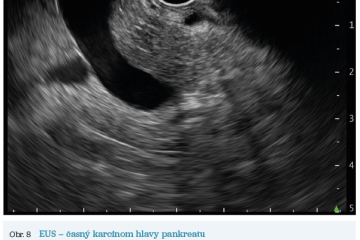

EUS umožňuje přesné vyšetření pankreatu. Lze také identifikovat a vyšetřit regionální lymfatické uzliny a vztah pankreatických lézí k okolním cévním strukturám. EUS může také sloužit jako navigace k odběru bioptického materiálu k cytologickému a histologickému vyšetření.21 AI je zde využívána k potvrzení malignity v IPMN. Kuwahara a kol. dosáhli s využitím 3 970 snímků a CNN algoritmu velké úspěšnosti v diferenciaci benigní a maligní IPMN s AUC 0,98.22 Řada studií se již zabývala AI asistovaným rozlišením chronické pankreatitidy a karcinomu pankreatu s AUC 0,940–0,986.23,24 Velká studie obsahující 1 174 461 snímků z celkem 583 případů hodnotící rozlišení autoimunitní pankreatitidy, karcinomu pankreatu, chronické pankreatitidy a normálního pankreatu dosáhla pro karcinom pankreatu AUC 0,97625 (obr. 6–9).